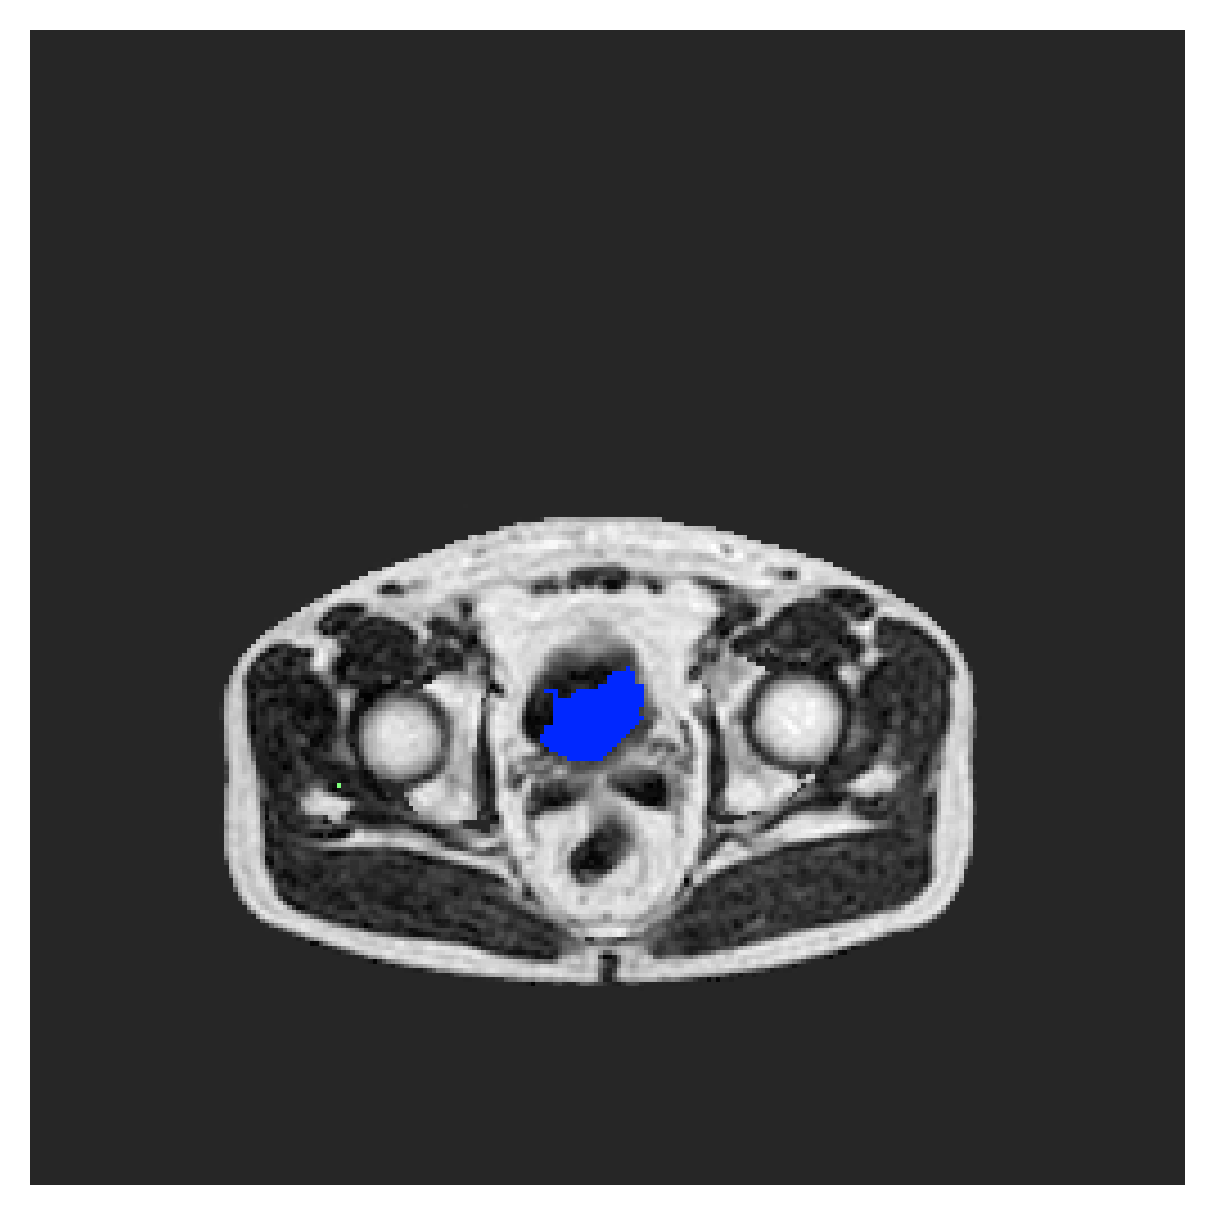

We normalize the volumes and resize the slices to pixels. As the official dataset comes with full annotations, we create a synthetic point ground truth. This is done by first randomly choosing the centers of the point annotations within the class masks, followed by filling an ellipse with axes lengths of and (in pixels) around each center. The intersections of these elliptic discs with the underlying full annotations are then used as our point ground truth. See Figure 2 for an example of the created weak annotation mask. The point annotations are created for every slice, one for each foreground object present in the slice.

The images contain two channels, one for water and one for fat content. For training, we normalize the volumes (per channel) and use 2D slices in the coronal plane, sized . The weak annotations are created synthetically, following the same procedure as described for the ACDC dataset.

5.2 Abdominal organ segmentation

In Table 3, the average DSC and HD95 results are shown (both using 2D and 3D distance maps) for the task of abdominal organ segmentation in POEM data (for boxplots see figures 8 and 9). We see that training with and (with distances calculated on 2D slices) performs comparably, while using and produces lower scores in both DSC and HD95 metric. On this dataset, the CRF-loss is able to compete with the boundary loss-based training strategies, even outperforming them on most classes. Most notably, all models trained with boundary loss appear to have a hard time segmenting the liver. We hypothesize this may be due to extremely severe class imbalance, as the liver covers a very large area compared to the rest of the classes. It is thus also more strongly affected by undersegmentations.

5.2.1 Qualitative comparison